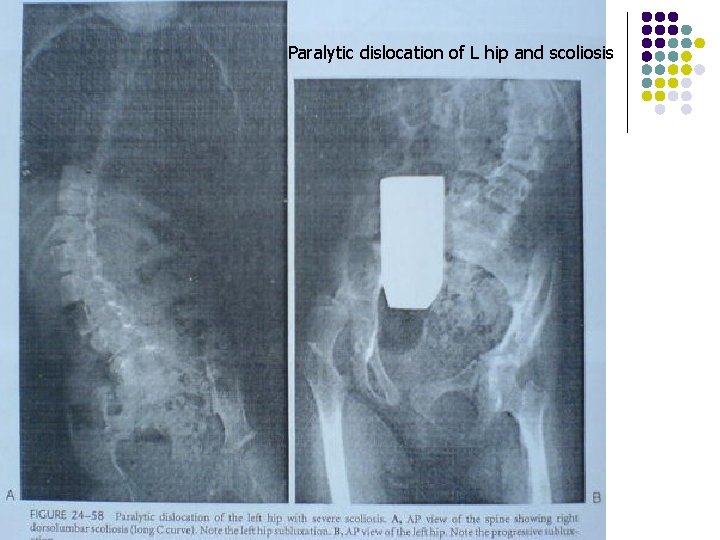

Paralytic dislocation of L hip and scoliosis

Hip subluxation/dislocation. . …surgery The next question to be asked is, does hip subluxation or dislocation lead to scoliosis? The conclusion is that there is a strong tendency for unilateral hip subluxation to occur in conjunction with pelvic obliquity, with most dislocations on the high side of pelvis. Surgical treatment is divided into three phases: I. Soft tissue surgery for the hip at risk. II. Reduction and reconstruction of the subluxated or dislocated hip. III. Salvage surgery for long standing painful dislocation.

scoliosis v v v Affecting between 25 -68% of patients with cerebral palsy. Incidence is highest in non ambulatory patients, and who have total body involvement. Patients with spasticity are at high risk, compared to other movement disorders. The usual curve pattern is a long sweeping curve that extends to the pelvis. with the apex of the curve at the thoracolumbar junction. Rotation accompanies the coronal plane curvature. Scoliosis leads to difficulty in sitting, and in using wheel chair. with: pressure sores on ischium teberosities, and a hand dependent sitter.